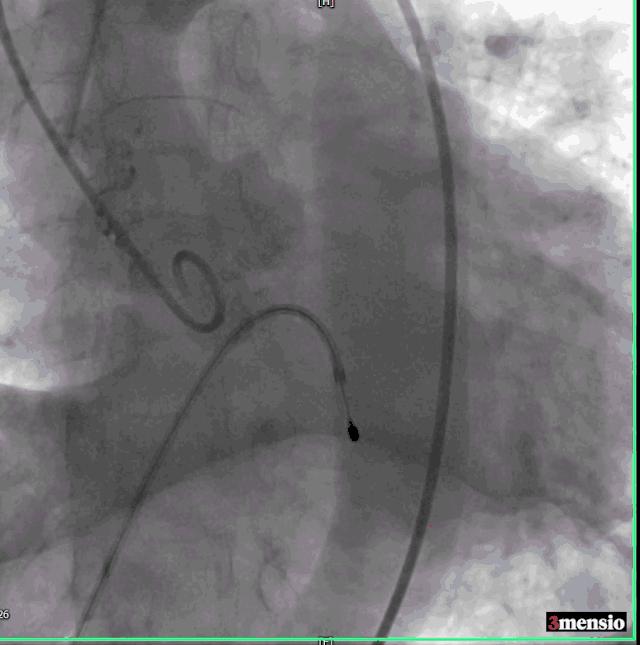

左侧穿刺股静脉,植入6F血管鞘,预留临时起搏器。追加肝素3000u,右侧预留2把ProGlide缝合器,并更换8F血管鞘。左侧股动脉经泥鳅送6F猪尾导管到升主动脉,行主动脉根部造影示主动脉瓣钙化,重度狭窄。

第一次造影